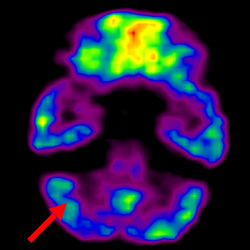

細(xì)胞治療前 PET CT 掃描顯示神經(jīng)組織中的藍(lán)/黑色區(qū)域,表明腦癱引起的大腦損傷。

細(xì)胞治療后,藍(lán)色和黑色區(qū)域減少,并且看到更活躍的區(qū)域。這表明損傷減少并改善了大腦功能。

這證明細(xì)胞療法是治療腦癱兒童安全有效的方法。細(xì)胞療法可以更新大腦損傷的核心,并且可以通過 PET CT 掃描來監(jiān)測大腦的改善情況。這些細(xì)胞療法與標(biāo)準(zhǔn)治療一起促進(jìn)腦癱兒童的生長和改善。